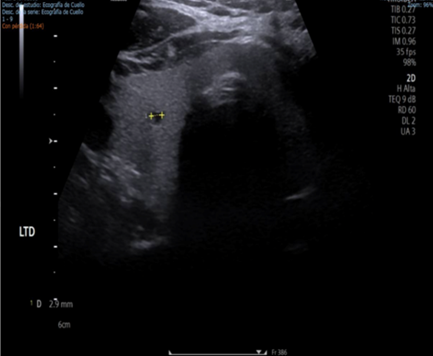

After evaluation by our unit and the thyroid pathology surgical department, a study of the thyroid gland was completed, with normal thyroid axis hormone levels and a thyroid ultrasound finding a 3-mm colloid cyst in the right thyroid lobe (Figure 3). After these results, a second intervention was decided upon to perform a total thyroidectomy and central neck dissection. The histological result indicated papillary carcinoma in the left thyroid lobe measuring 5 mm. Having a final stage of papillary thyroid carcinoma (pT4pN2M0). Subsequently, adjuvant therapy with radioiodine was decided. Currently, the patient is under clinical follow-up by our department.